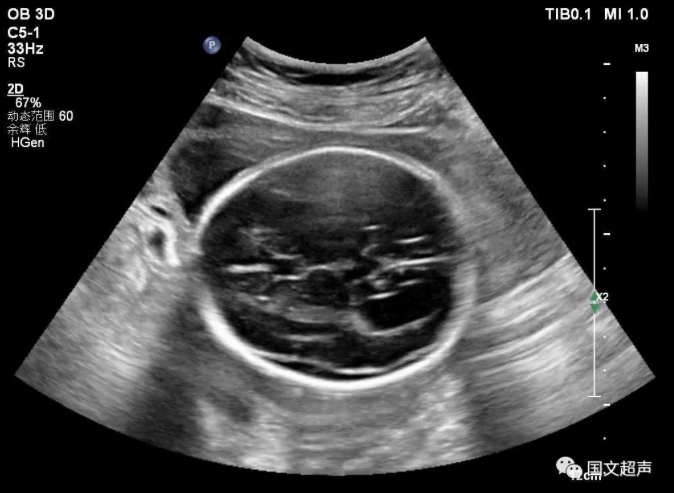

一.關(guān)于側(cè)腦室

側(cè)腦室后角寬度>10mm為腦室輕度擴(kuò)張,而寬度>15mm時(shí)即可診斷腦積水,若側(cè)腦室后角寬度<10mm,則應(yīng)考慮其為正常的超聲表現(xiàn)。

大部分輕度腦室擴(kuò)張的胎兒預(yù)后良好,但約有20%的輕度側(cè)腦室擴(kuò)張?zhí)嚎珊喜⒂腥旧w異常、其他顱內(nèi)外異常等問(wèn)題而出現(xiàn)智力或發(fā)育障礙,甚至在圍生期即死亡。